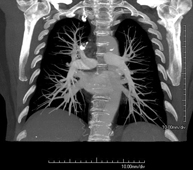

- Pulmonary Artery CT angiography (PTE Study, Pulmonary Thromboembolism)

Diagnostic test to examine the pulmonary arteries using CT (Computed Tomography) equipment to obtain two- and three-dimensional images. This requires the use of an iodinated contrast agent, which will provide improved anatomical definition. This test is mainly indicated in cases of suspected pulmonary thromboembolism (PTE) to rule out or confirm the presence of blood clots inside the arteries.